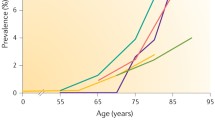

Calcific aortic valve disease is the most prevalent cause of aortic stenosis (AS) worldwide and poses a significant disease burden, with AS being the third most common cardiovascular problem after coronary artery disease and hypertension [2]. Prevalence of aortic sclerosis increases with age and the rate of progression to AS is estimated to be 1.8-1.9% of patients per annum [3]. Calcific AS has an estimated prevalence of 0.4% in the general population and increases to 1.7% in those aged >65 years in developed countries [4].

The prevalence of MAC has been reported to be between 8% and 15% and increases with age [8, 9]. Risk factors are generally similar to those in atherosclerosis and calcific aortic valve disease with a few other specific risk factors including female gender, chronic kidney disease and congenital metabolic disorders such as Marfan syndrome and Hurler syndrome [10,11,12].